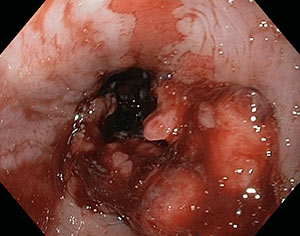

Tumori maligni:

A seconda dell’epitelio di origine si possono avere due tipi di carcinoma esofageo:

squamo-cellulare e adenocarcinoma

Esofagogastroduodenoscopia con biopsie che documentano la natura della lesione